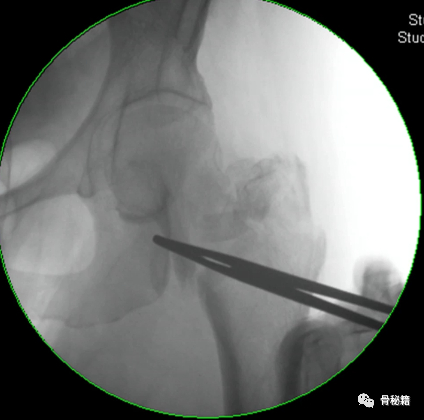

2、股骨干部复位,工具比不可少,主要是金手指

复位时注意要用一些肌松和适当的牵引

很多时候金手指不太听话这个时候可以试试顺时针和逆时针旋转

3、保持复位,我们知道在扩髓时保持复位非常重要,可以用一些辅助器械来进行辅助保持复位。

对于B型骨折的蝶形骨块如果不保持复位可能扩髓之后会离的很远影响骨折愈合

对于A1.3型骨折,单纯牵引很难复位通常需要借助骨钩来复位,主要是由于小粗隆完整受到肌肉的牵拉而移位

可以在偏前方植入一枚克氏针临时固定来进行复位辅助